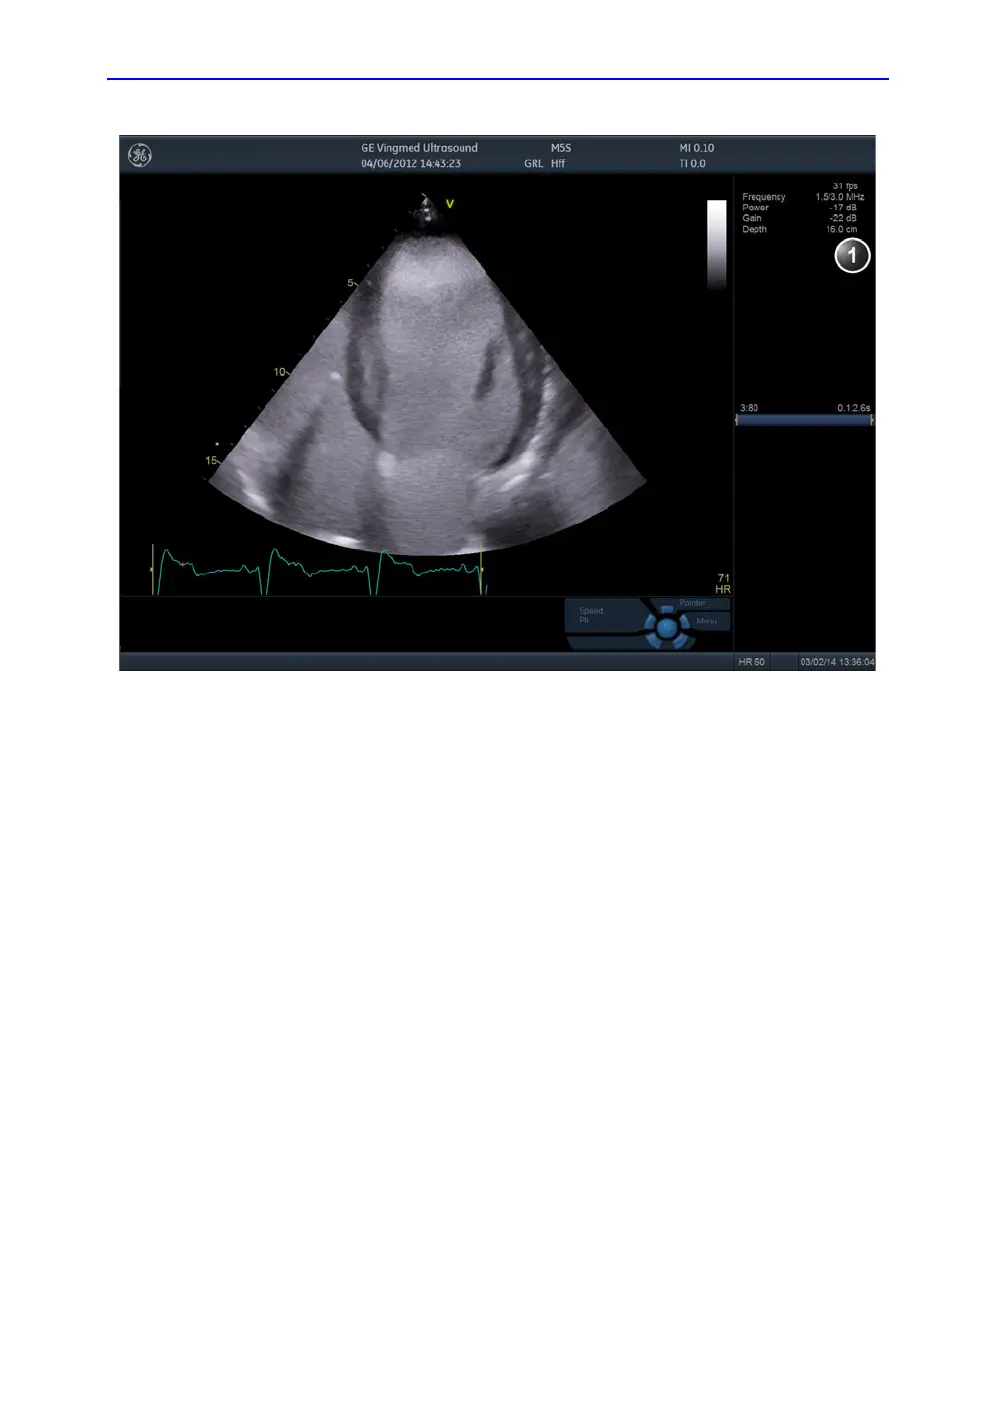

Figure 5-21. The LV Contrast acquisition screen

1. Parameter window